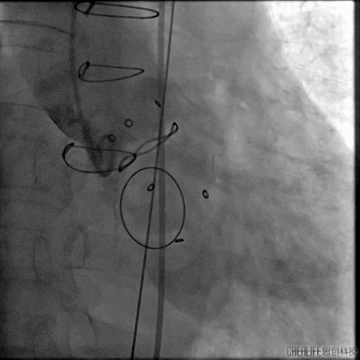

瓣上造影

造影可见主漏及无窦附近明显瓣周漏;

跨瓣建立轨道

主动脉瓣架植入

根据造影情况决定选择VenusA 23号瓣膜

主动脉瓣架释放

复查造影